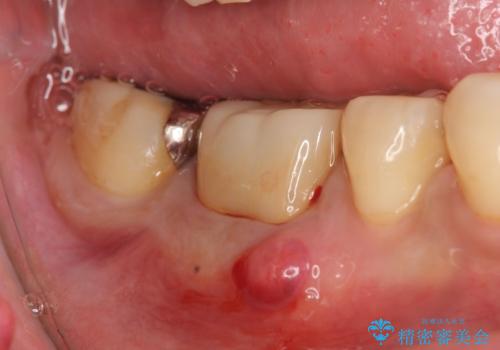

40代女抜歯適応の歯を保存した一例

虫歯が骨より深い位置まで到達しているため、本来であれば抜歯の適応となる歯ですが、「いずれ抜歯になってしまってもよいので少しでも長く使いたい」という希望により、治療をおこないました。

部分矯正により歯を引っ張り出すことで、健康な歯を歯ぐきのレベルまで持ち上げます。

およそ1か月で目標レベルまで出てきたため、1か月保定した後土台をたてて被せものを製作しました。頭でっかちな構造のため良い経過は期待できないので、保険内での治療も提案しましたが、目立つ部位であったため相談の上、審美的に回復しました。

被せものの種類:e.max プレスクラウン (エコノミー)

今回のように、抜歯適応であっても炎症が無い場合は無理やりにでも保存する意義はあるかもしれませんね。